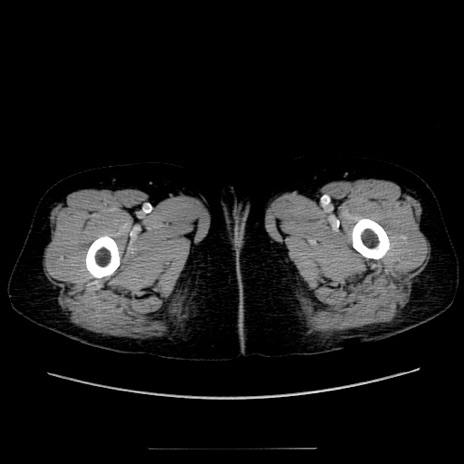

【症例】70歳代女性

【主訴】お腹が張る

【現病歴】1週間くらい前から腹部膨満の自覚あり。昨日夜から増悪したため、本日救急外来受診。

【身体所見】意識清明、BT 36.5℃、BP 165/106mmHg、HR 80bpm、SpO2 98%、腹部:膨満、軟、自発痛・圧痛なし、触診にて不快感あり、腸蠕動音:減弱

【データ】WBC 12600、CRP 1.04